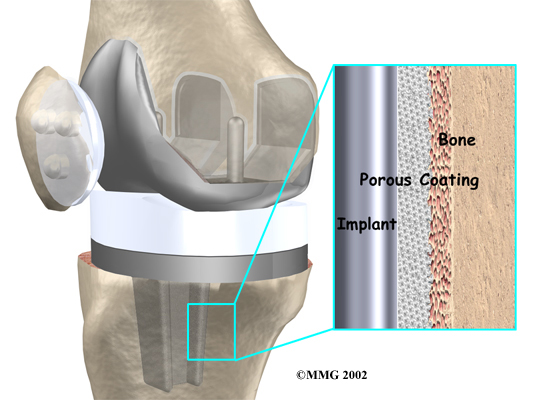

A cemented prosthesis is held in place by a type of epoxy cement that attaches the metal to the bone. An uncemented prosthesis has a fine mesh of holes on the surface that allows bone to grow into the mesh and attach the prosthesis to the bone.

The metal femoral component is then placed on the femur. In the uncemented prosthesis, the metal piece is held snugly onto the femur because the femur is tapered to accurately match the shape of the prosthesis. The metal component is pushed onto the end of the femur and held in place by friction. In the cemented variety, an epoxy cement is used to attach the metal prosthesis to the bone.

The metal tray that holds the plastic spacer is then attached to the top of the tibia. This metal tray is either cemented into place, or held with screws if the component is of the uncemented variety. The screws are primarily used to hold the tibial tray in place until bone grows into the porous coating. (The screws remain in place and are not removed.)